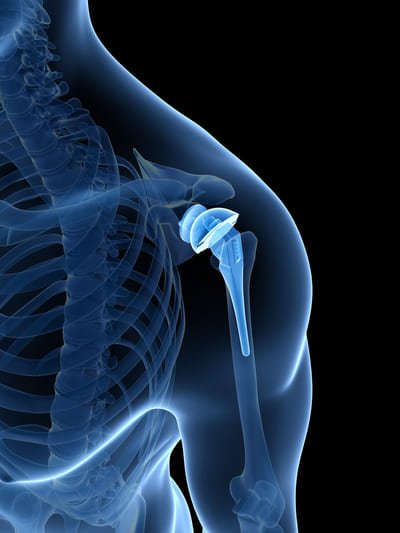

Prótesis de Hombro

Sustitución de la articulación del hombro para restaurar función y aliviar dolor.